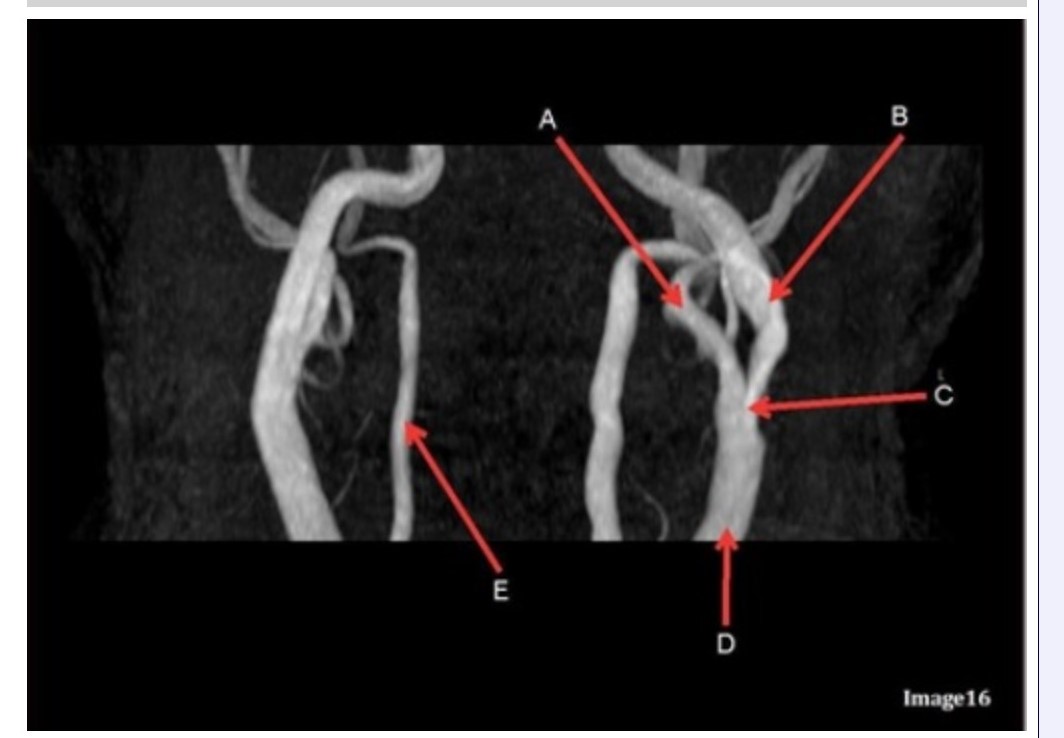

Letter B in Image 16 is pointing to:

A. Internal carotid artery

B. External carotid artery

C. Vertebral artery

D. Common carotid artery

E. Common carotid bifurcation

Letter E in Image 16 is responsible for blood supply to the:

A. Anterior brain

B. Posterior brain

C. Face

D. Upper extremities

Letter D in Image 16 is pointing to:

A. Internal carotid artery

B. External carotid artery

C. Vertebral artery

D. Common carotid artery

E. Common carotid bifurcation

Image 16 is an example of what type of MR image?

A. MR spectroscopy

B. MRA Circle of Willis

C. MRV intracranial circulation

D. MRA extracranial circulation

E. MRA intracranial circulation

Letter B in Image 16 is responsible for blood supply to the:

A. Anterior brain

B. Posterior brain

C. Face

D. Upper extremities

Letter E in Image 16 is pointing to:

A. Internal carotid artery

B. External carotid artery

C. Vertebral artery

D. Common carotid artery

Letter C in Image 16 is pointing to:

A. Internal carotid artery

B. External carotid artery

C. Vertebral artery

D. Common carotid artery

E. Common carotid bifurcation

Letter A in Image 16 is pointing to:

A. Internal carotid artery

B. External carotid artery

C. Vertebral artery

D. Common carotid artery

E. Common carotid bifurcation

Which arteries join together to form the basilar artery?

A. Vertebral arteries

B. External carotids

C. Internal carotids

D. Iliacs

E. None of the above

Letter A in Image 16 is responsible for blood supply to the:

A. Anterior brain

B. Posterior brain

C. Face

D. Upper extremities